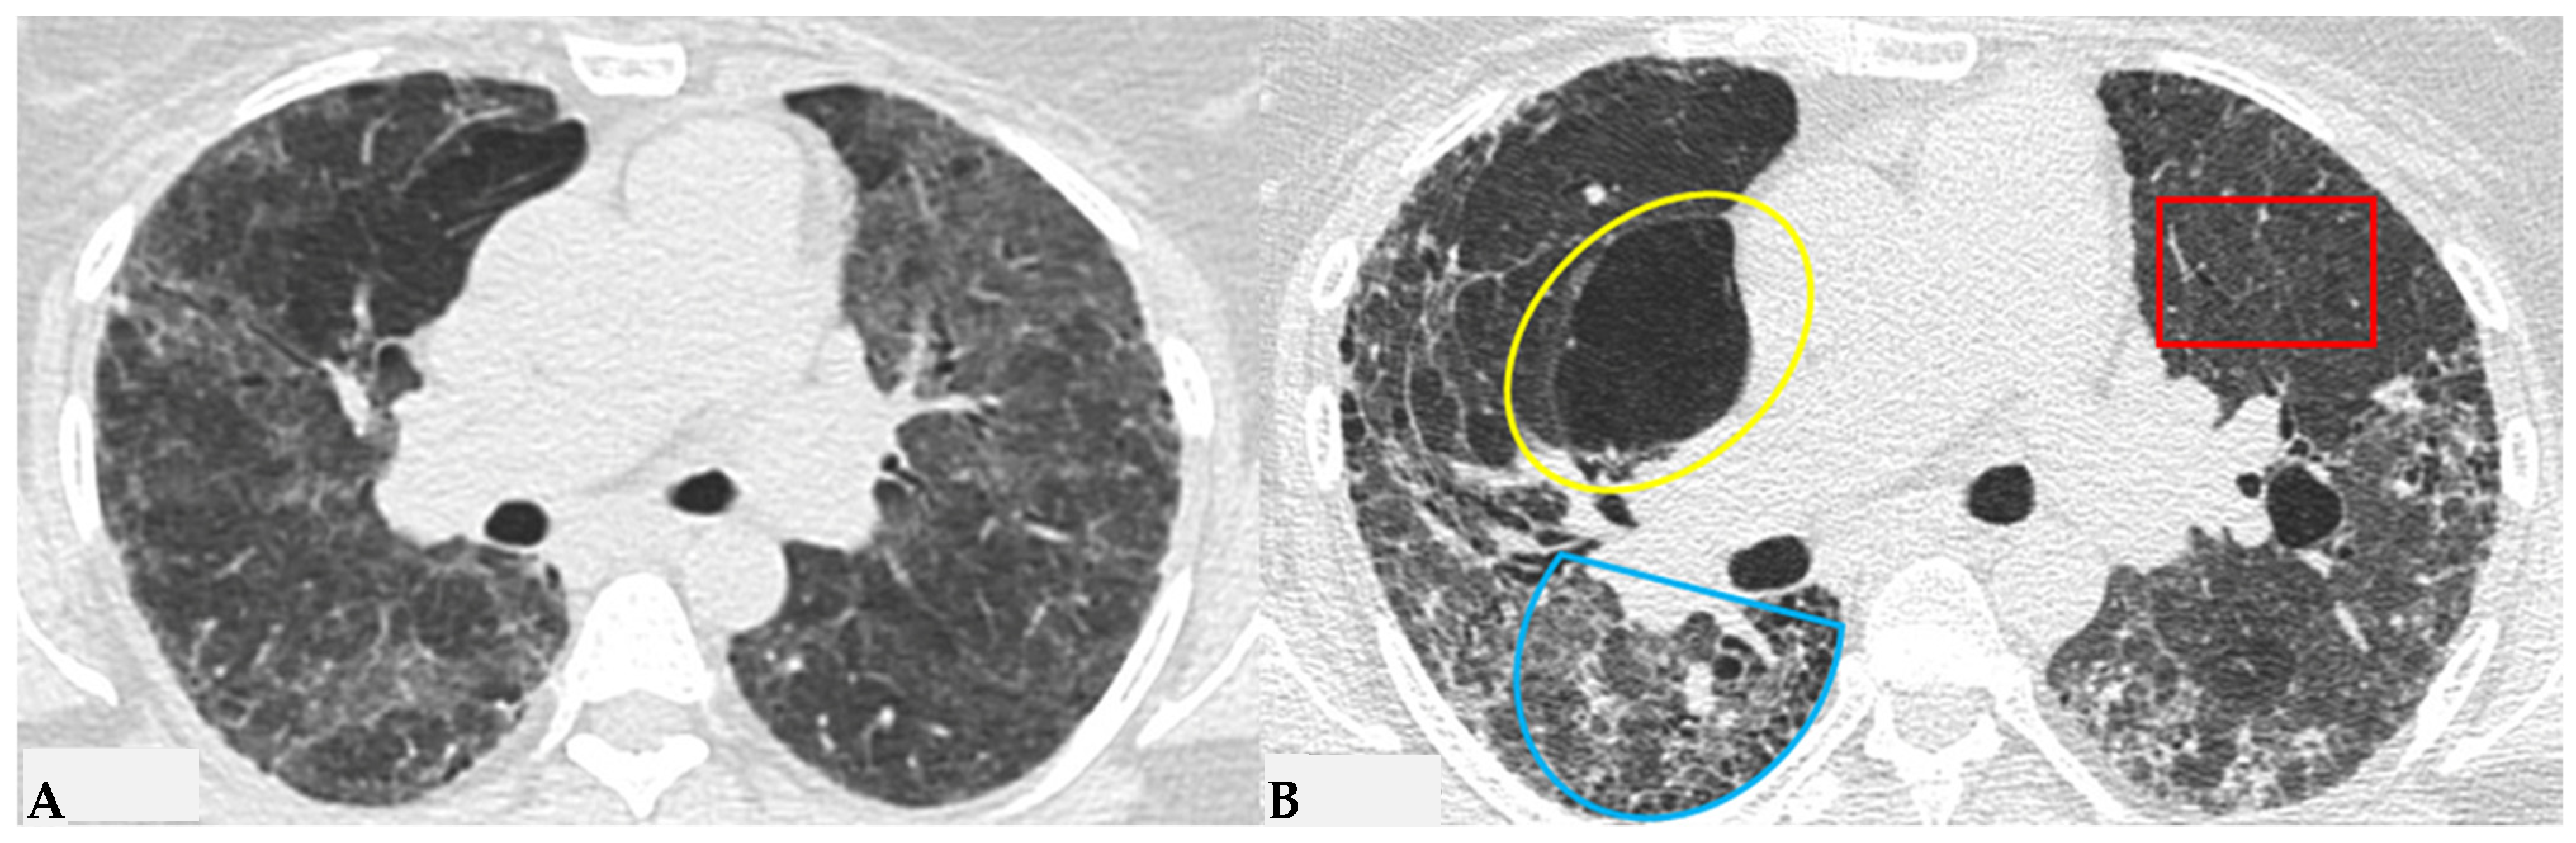

Semeiotic features classified as “indeterminate for FHP pattern” encompass the truly indeterminate HRCT pattern (Figure 9), fibrotic NSIP (Figure 10) and OP. Additionally, due to the primarily bronchocentric nature of the initial damage, the evolution of the fibrotic radiological features may reveal a characteristic centrifugal appearance in MPR reconstructions, with alterations in GGO/consolidative distortive fibrotic changes typically distributed centrally, sometimes sparing the subpleural anatomical surfaces. The patterns outlined in the latest international reference guidelines for HP result from a conclusive diagnostic multidisciplinary approach undertaken in the previous IPF guidelines of 2018 [10]. This correlation addresses the need to introduce a universal language, shared among specialists, that encompasses clinical, radiological and pathological aspects. This ensures the optimal finalization of a diagnostic-therapeutic process for better understanding and simplification [9,10,11]. HP is also coined “the great mimicker”, as it represents a deceptive disease from multiple perspectives; the presence of sometimes hidden antigens makes early diagnosis challenging. The disease course can be deceptive, resembling various pathologies. Without a comprehensive diagnostic panel, including thorough clinical and medical history evaluation, along with functional data and chest HRCT for pattern interpretation, untreated acute cases may progress to severe conditions. This includes the development of fibrotic ILD with end-stage terminal patterns, leading to a secondary but unfavorable outcome of pulmonary fibrosis. In addition to these respiratory complications, pulmonary arterial hypertension (PAH) may develop as a secondary condition to ILD, further compromising the patient’s prognosis. Therefore, it seems appropriate to integrate pneumological and radiological specialist examinations with cardiac evaluations, particularly echocardiography as an initial step, to obtain a diagnostic estimate of pulmonary arterial pressure. This information, in conjunction with complete clinical-functional-diagnostic data, is essential for the treatment of delicate and advanced forms of fibrotic HP with secondary PAH, especially considering the significantly different outcomes of patients with secondary PAH due to FHP [11,12,13,14,15,16].

Truly indeterminate HP pattern. Chest HRCT, axial scan HRCT pattern characterized by mild fibrotic changes of a limited extent with patchy GGO in the upper lobes (A); the lower lobes show GGO, fine reticulations with modest mosaic attenuation and rare traction bronchiectasis/bronchiolectasis (B) with a “truly indeterminate” pattern according to new HP guidelines (2020) [4].

f-NSIP pattern: chest HRCT, axial scan. Mild fibrotic changes of limited extent with a greater distribution in the upper lobes with superimposed GGO (A); the lower lobes show marked extension of GGO, fine reticulations with traction bronchiectasis/bronchiolectasis (B); “fibrotic NSIP pattern” according to new HP guidelines (2020) [4].